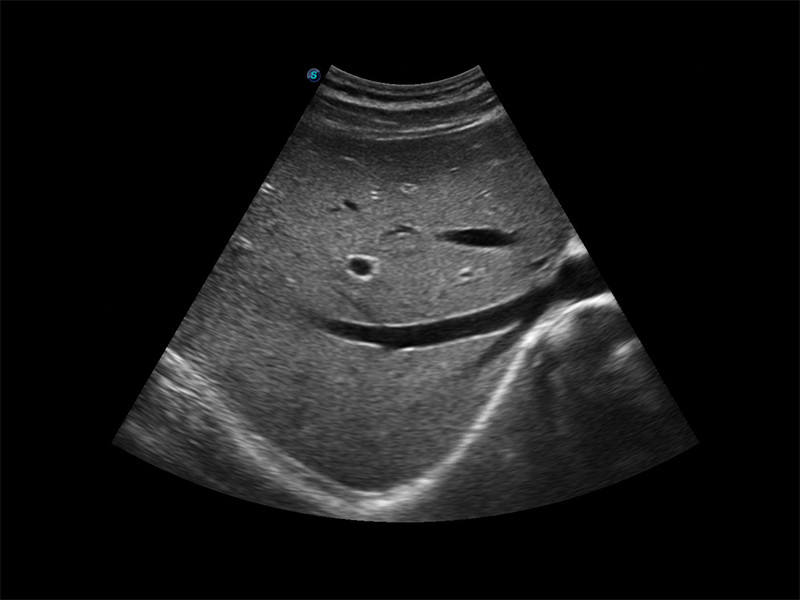

Sonda de Endocavidade 6V1

A sonda endocavitária pode enfrentar aplicações em ginecologia, urologia,

próstata, e sua tecnologia de detecção de temperatura não apenas protege o

paciente, mas também prolonga a vida útil.